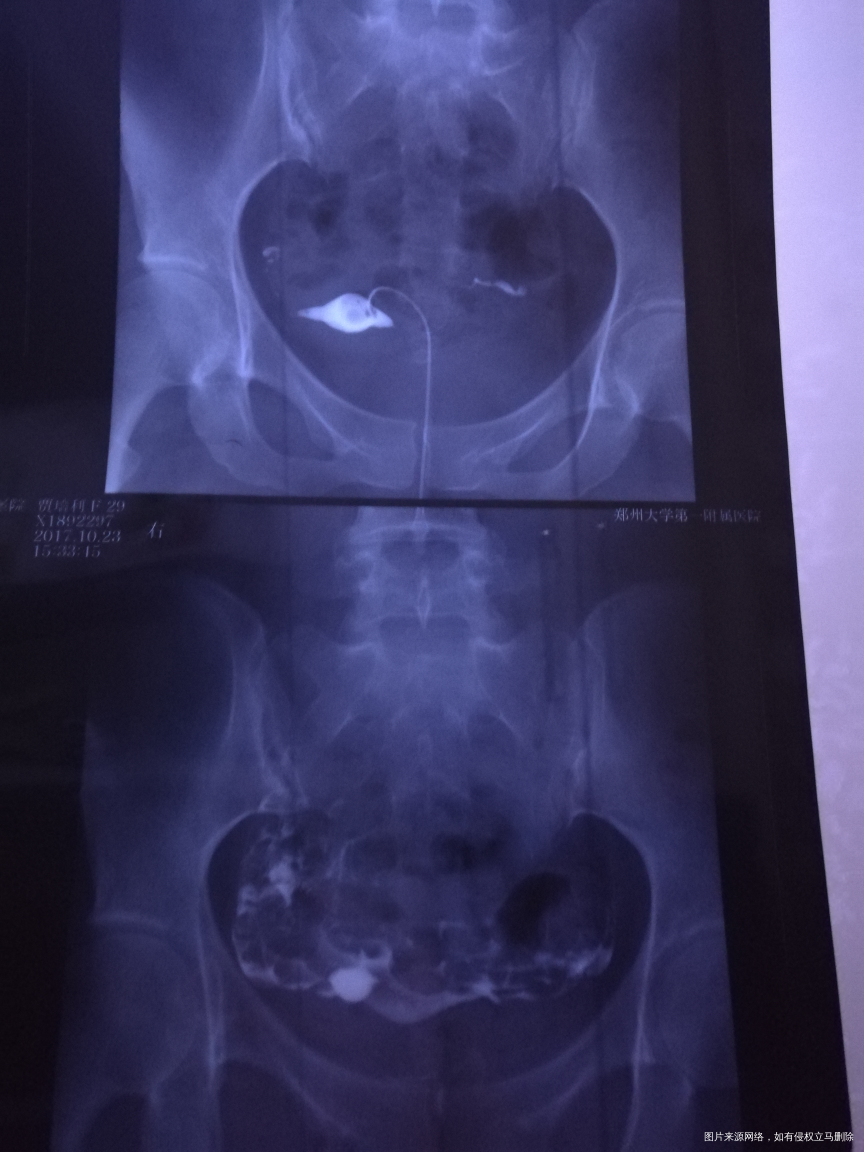

有没有问题,右侧上举严重不???影不影响怀孕?自己备孕两年多了?

您好,双侧输卵管通畅的,可以怀孕试试

天边 回复 赵敏英:右侧是不是有点粘连,上举

考虑盆腔有点粘连可以考虑行腹腔镜手术,建议结合您年龄等综合考虑,祝您好孕,欢迎咨询,满意请点击采纳

你好,输卵管上举是会影响到怀孕的。